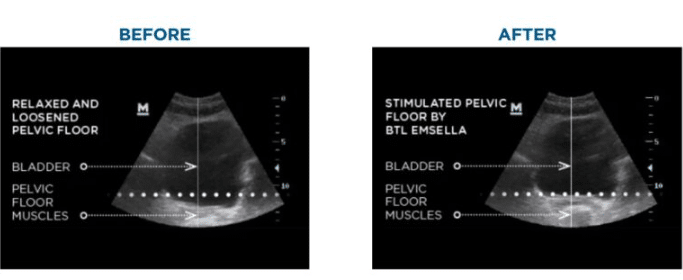

Before & After